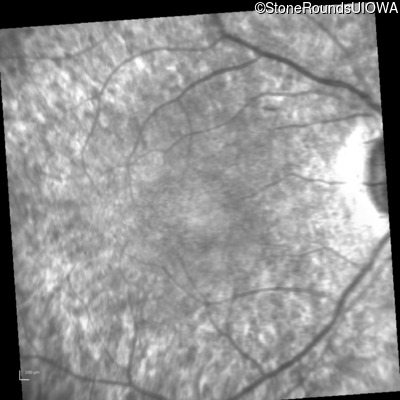

Visit at age: 21 years

Infrared Fundus Photograph - Left - 20/32

Exemplar